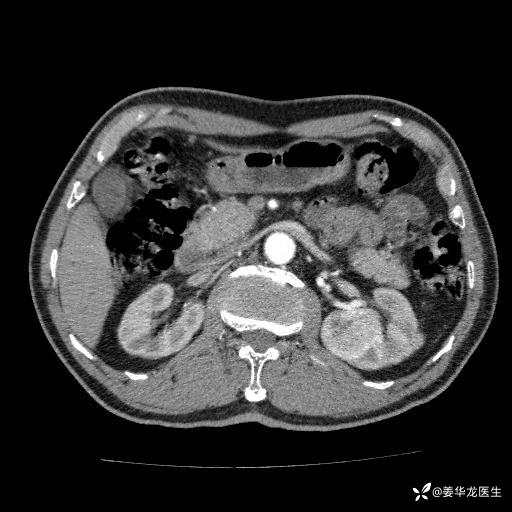

左肾中心型肾门部肿瘤39mm×34mm×36mm,右肾GFR25ml/min,部分切还是全切?

患者75岁老年男性,体重50kg,无高血压、肾病、糖尿病等基础病,检查发现左肾中心型肾门部肿瘤,右肾GFR只有25ml,无肉眼血尿,无镜下血尿。入院验血常规检查均正常,包括肾功能,肌酐102.7umol/L.

二、左肾肿瘤与左肾集合系、左肾动静脉关系密切,左肾部分切除术可行吗?成功率有多大?成功部分切后,肾功能还有多少?

三、患者无任何基础病,为什么右肾GFR只有25ml/min,反尔有肿瘤的左肾GFR达38.8ml/min?